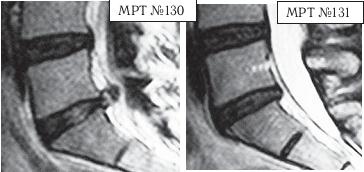

На МРТ № 128 наблюдается состояние поясничного отдела позвоночника после операции: рецидив грыжи межпозвонкового диска в сегменте LV-Sr с отрывом секвестра и его миграции в краниально-дорсальном направлении, разрыв задней продольной связки. На МРТ № 129 наблюдается состояние поясничного отдела позвоночника после лечения методом вертеброревитологии: отсутствие грыжи межпозвонкового диска в сегменте L — S. В межпозвонковых дисках в сегментах LIV-LV, L — SI наблюдается процесс репаративной регенерации. ![]() На МРТ № 130 наблюдается состояние поясничного отдела позвоночника после двух хирургических операций: рецидив грыжи межпозвонкового диска в сегменте LV-SI. На МРТ № 131 наблюдается состояние поясничного отдела позвоночника после лечения методом вертеброревитологии. Рецидив грыжи межпозвонкового диска после двух хирургических операций — и это у молодого человека в возрасте 16 лет! Чрезмерное увлечение компьютером, малоподвижный образ жизни основательно подорвали его здоровье. Всё это привело к тому, что в течение года, начиная с пятнадцатилетнего возраста, он практически не выходил из больниц. После первой хирургической операции на позвоночнике, менее чем через месяц, боли возобновились. Спустя два месяца его вновь прооперировали по поводу рецидива — грыжи межпозвонкового диска. После второй хирургической операции боли наблюдались практически два месяца подряд, потом затихли, но полностью так и не прошли. Через пять месяцев появилась слабость в обеих ногах. Сделали снимки МРТ, диагностировали рецидив грыжи межпозвонкового диска, естественно рекомендовали сделать очередную третью хирургическую операцию. В промежутках между операциями молодой пациент несколько раз находился на стационарном лечении в неврологическом отделении городской больницы. Именно там, после того как у парня была диагностирована очередная грыжа, лечащий врач посоветовал не спешить с третьей операцией и порекомендовал ему обратиться ко мне в клинику. Конечно, этот случай был далеко не простым и пришлось основательно потрудиться как мне, так и самому пациенту над восстановлением его здоровья. Но зато результат порадовал всех тех, кто непосредственно участвовал в этом процессе, и кто косвенно ему способствовал. Можно сказать, ещё одна судьба была изменена и молодой человек спасён от инвалидной коляски. МРТ № 132МРТ № 133 ![]() На МРТ № 132 и МРТ № 133 — увеличенные фрагменты МРТ № 130 межпозвонковых дисков в сегментах LIV-LV и LV—SI до лечения методом вертеброревитологии. Структура межпозвонковых дисков неоднородна. ![]() На МРТ № 134 и МРТ № 135 — увеличенные фрагменты МРТ № 131 межпозвонковых дисков в сегментах LIV-LV и LV—SI, после лечения методом вертеброревитологии. Наблюдается весьма интересное явление — репаративная регенерация. Обратите внимание, насколько уменьшилось количество некрозной (мёртвой) ткани и увеличилось функциональной (живой) ткани. Примечательно, что хондроциты при регенерации в данной фазе формируют вертикальные и наклонные «колонны» согласно вектору нагрузки на межпозвонковый диск в районе фиброзного кольца. В центре межпозвонкового диска наблюдается не менее интересное явление — начало регенерации пульпозного ядра! Следующий случай можно назвать абсолютно беспрецедентным в истории науки вертебрологии и новым этапом в развитии вертеброревитологии. С помощью метода вертеброревитологии удалось практически полностью восстановить (по сути заново вырастить) отсутствующий межпозвонковый диск! И это без всяких химических препаратов, а исключительно благодаря естественному восстановлению биомеханики позвоночника — выстраиванию определённой биомеханической конструкции. При построении последней были достигнуты оптимальные условия для активизации резервных возможностей организма, что, в свою очередь, способствовало запуску репаративной регенерации вплоть до реституции диска, который в своё время был практически полностью удалён. Это удивительное явление, сравнимое разве что с реанимацией. Впрочем, всё по порядку. |